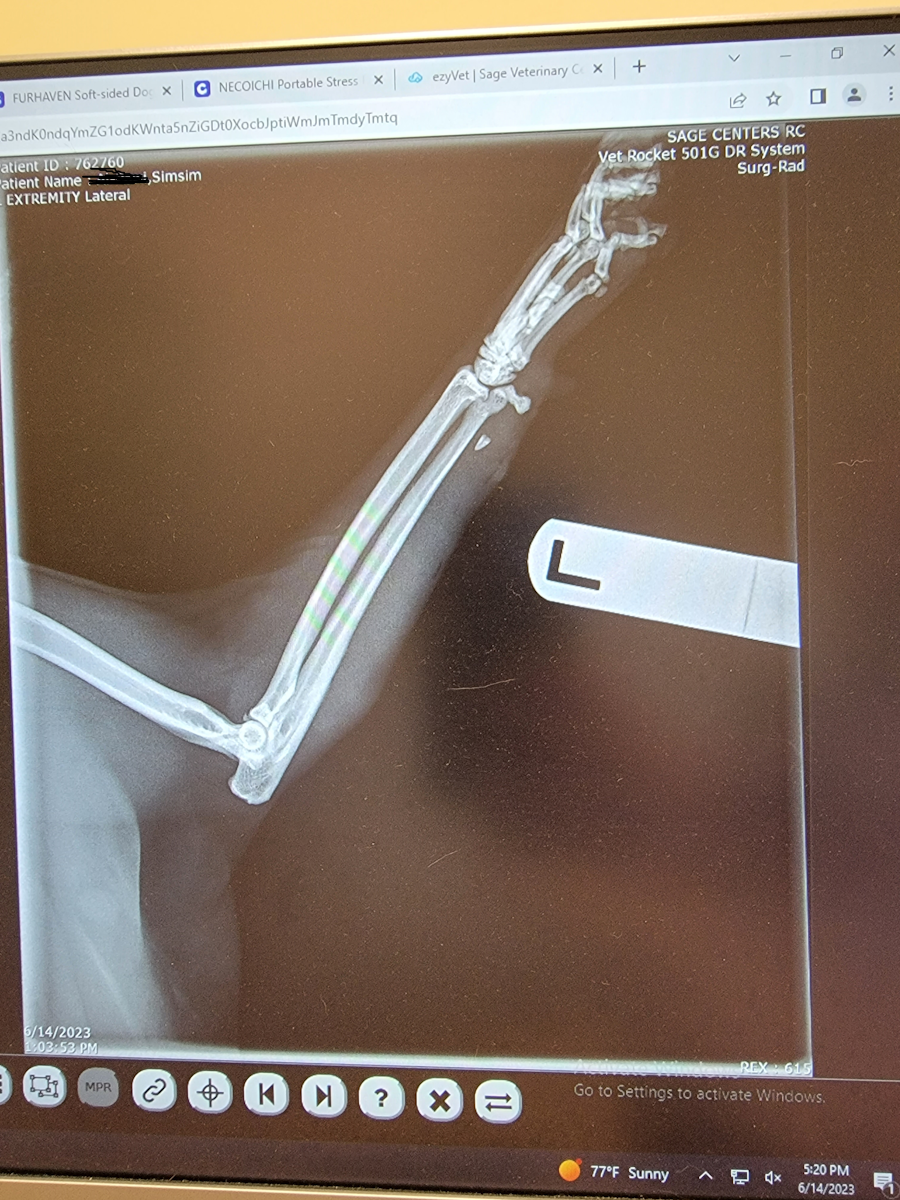

Our cat has been limping for a few days (we recently had to move some furniture around and I think he might have knocked something over onto himself) so we finally took him to the ER. He’s a big indoor/outdoor boy and usually if he limps for a bit he gets better in a day or so if we move his stuff into a place where he doesn’t have to leap around. They had to have us do a drop-off and he was not having it.

So, no shit, but there was another cat’s TOOTH embedded in Simsim’s leg. The veterinarian said that it was very close to a tendon. They got it out, but he needs to be in a cast and cone for 4 weeks. Poor little guy. They’re having me give him buprenorphine and gabapentin for pain.